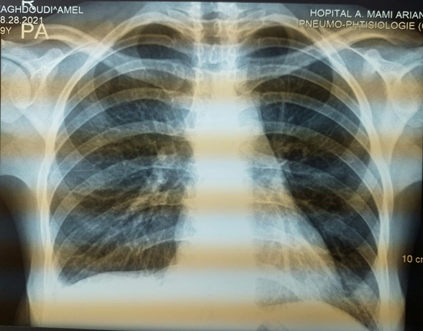

The chest X-Ray showed an enlargement of the middle mediastinum associated to pleural effusion opacity, but any active pulmonary lesions (Figure 1). A computed chest tomography revealed the presence of a parietal mass centered on the sternum, with extension in the soft parts, bone lies of the sternal manubrium, lies of the vertebral hemi-bodies of T10 and T11, cervical lymph nodes, phrenic mediastinal and sub-pectoral nodes with peritoneal and mesenteric involvement (Figure 2). Magnetic resonance imaging of the spine showed tiered thoracic lumbar and sacral spondylitis with paravertebral and anterior epidural collections responsible for spinal cord compression next D10 without signs of spinal cord pain (Figure 3).

Figure 2 A-Chest computed tomography scan revealed a parietal mass centered on the sternum, with extension in the soft parts, bone lies of the sternal manubrium B- Mass centered on the right costovertebral gutters of the 10th and 11th ribs, lies of the vertebral homebodies of T10 and T11, right pleural effusion.